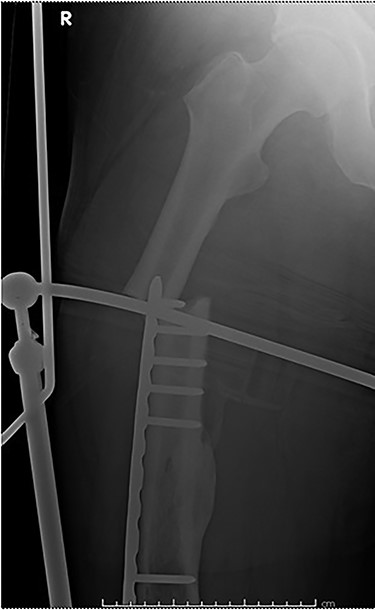

Case 2 (Figs 3–5): here difficulties were clearly encountered in achieving satisfactory reduction in the coronal plane. The screw immediately proximal to the fracture line is too close to the fracture.

Selecting a longer plate would have allowed proximal screws to sit more appropriately in order to reduce the risk of plate fatigue.